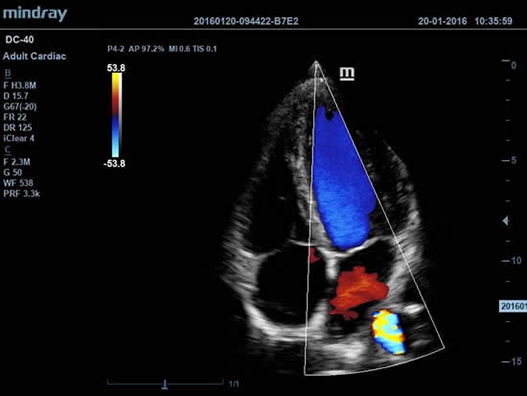

DC-40 имеет особое применение в кардиологической практике, благодаря функции Free Xros CM. Она позволяет отслеживать движения сердечной мышцы в различных фазах и одновременно определять синхронизацию миокарда. Это существенно повышает точность диагноза.

• Функции анатомического режима Free Xros M и Free Xros CM позволяют точно расчитывать анатомические параметры и отслеживать движения сердечной мышцы.

• Free Xros M™ - анатомический М-режим - это возможность вращения курсора в М-режиме под произвольным углом (при фиксированном положении датчика) и, соответственно, получения графика движения структур сердца в различных произвольных плоскостях;

• Free Xros CM™ - огибающий анатомический М-режим;